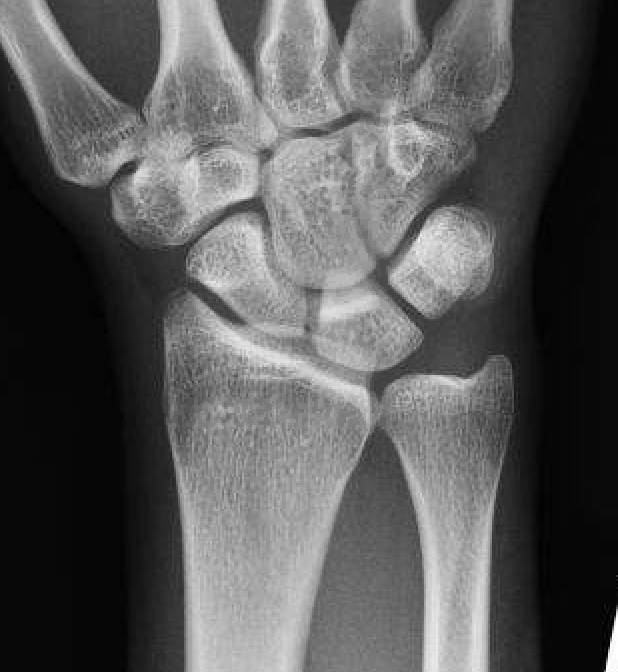

Xrays

Ulna variance

Wide variation in the population - increased load on TFCC with ulna positive

Xray in neutral supination / pronation

- variance is not static and varies up to 3 mm with wrist position

- ronation increases ulnar variance

- supination decreases variance

Transverse line of lunate fossa to transverse line of ulna head

Ulna neutral

Ulnar negative

Ulna positive